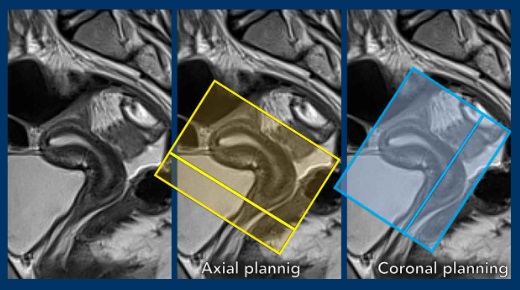

Sequence Planning

- The MR sequences are planned relative to the long axis of the cervical canal.

- The axial plane is perpendicular to the long axis of the cervical canal.

- The coronal plan is parallel to the long axis of the cervical canal.

Example showing how flexion, and in particular version impact sequence planning.

- In this case there is anteversion of the cervix and retroflexion of the uterus.

- Remember that in cervical cancer, the axial sequences are planned perpendicular to the cervical canal.